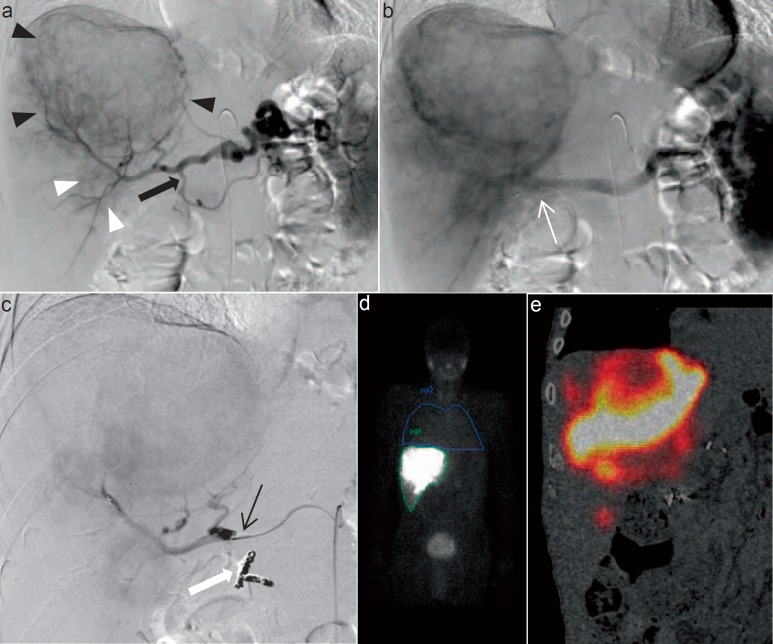

Abstract Image